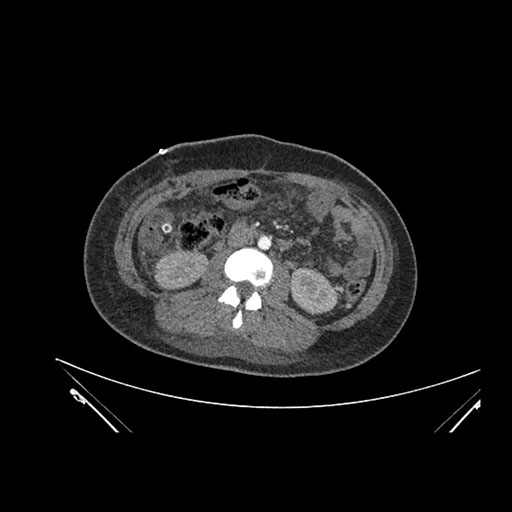

Imaging Analysis

Look through the patient's CT scan to identify any areas of concern for the necessary procedure.

Coronal Venous

Based on initial findings, which issue(s) would you be most concerned about?